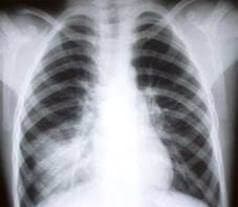

Kızamık sonrası orta kulak iltihabı (%7-9), zatürre (pnömoni) (%1-6), ensefalit (beyin iltihabı) (1/1000-1/2000) ve ölüm (1/10000) görülebilir. Komplikasyonlar döküntüden sonra ateşin uzun süre devam ettiği hastalarda daha sıktır. Çocuklarda ölümlerin %60’ından sorumlu olan pnömoni daha sıktır; ensefalit ise erişkinlerde daha sık görülür.